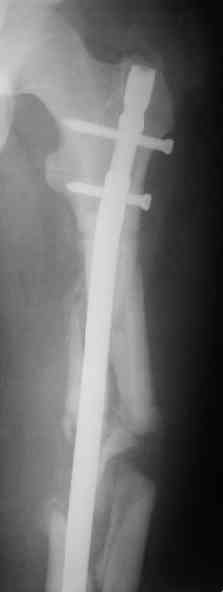

СМ> Если имеются под рукой Р-снимки, продемонстрируйте, плиз.

Вот несколько. С тисками и трубой на днях сделаем.